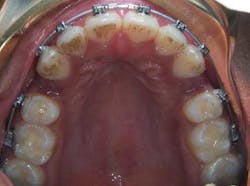

Therefore, the treatment plan for Rachael was based mainly on her facial appearance as opposed to any tooth irregularity. Despite the fact that there was no crowding, extraction of four bicuspids was still indicated, with the goal of creating space for retraction of the incisors.

Uprighting the incisors resulted in better facial balance, elimination of mentalis strain and retraction of the protruded lower lip.